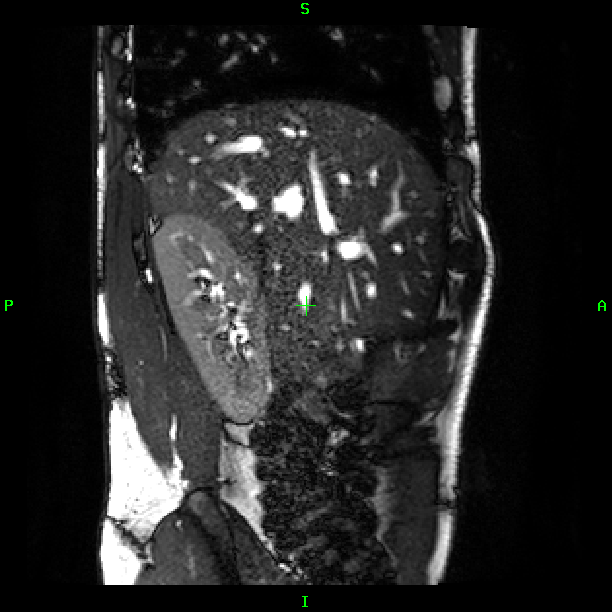

The reconstruction results of the abdominal scan is shown in Fig. 2. For single orientation acquisition motion artifacts are present in SVR reconstruction in spite of the automatic rejection of misaligned slices (b, e). On the other hand, SR reconstruction of slices (c, f) selected using our proposed method resolved most of the breathing artifacts. The bottom row demonstrate the proposed SRNN can accurately separate the inhale and exhale respiratory states.

![]() |

| (h) | (i) | (j) | (k) |